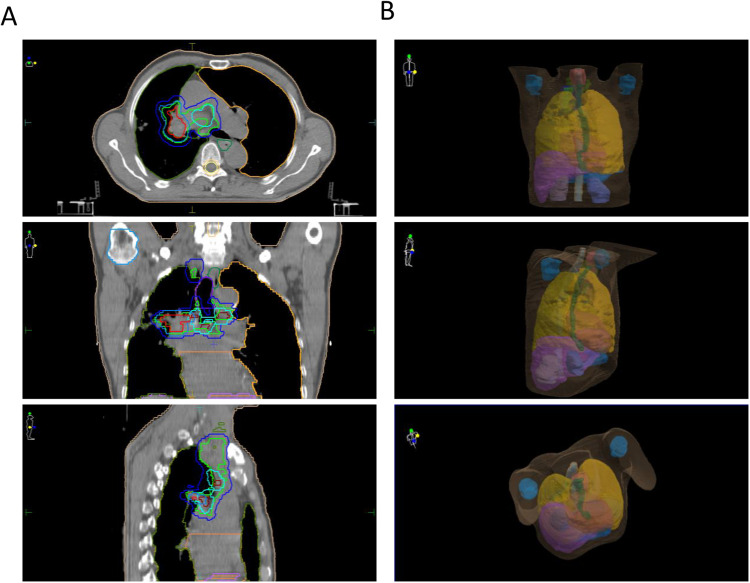

Abstract Image